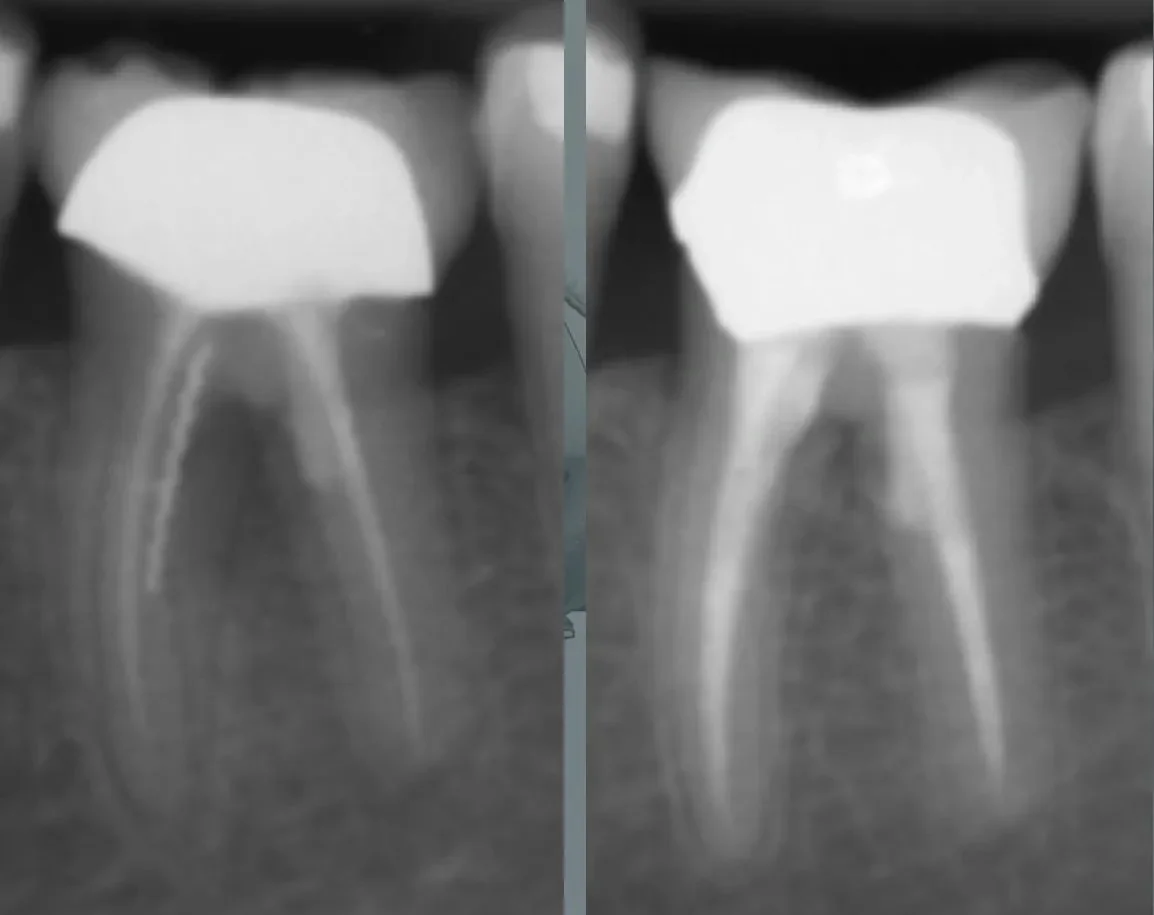

Root Canal Instrumentation

- Principles of mechanical and manual instrumentation

- Techniques for glide path creation, canal shaping, and cleaning

- Glide path creation and canal shaping using rotary and hand files on models

- Techniques for mechanical and manual cleaning